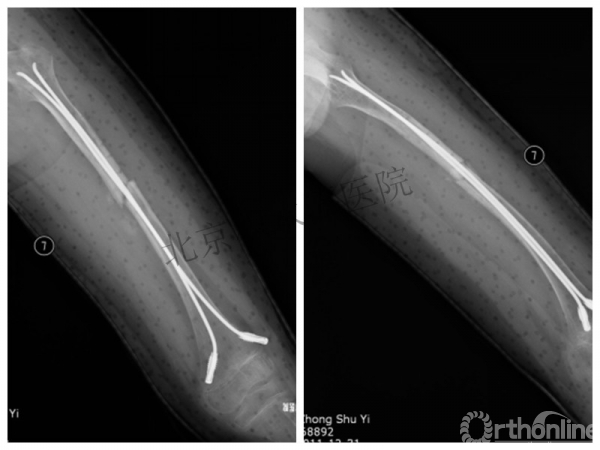

取板后再骨折→TEN

TEN取出后2个月

闭合复位再固定加尾帽